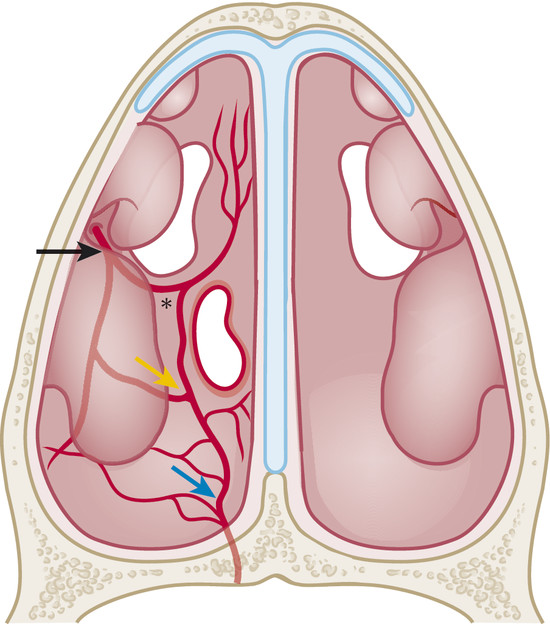

The nasal floor is a region that receives blood supply from different arteries. The posterior part is fed by the posterior septal artery, also known as nasal septal artery, which divides into two branches before reaching the nasal septum. The inferior branch runs toward the nasal floor and is the main artery of this flap. Laterally, this artery anastomoses with branches of the posterior lateral nasal artery, another main branch of the sphenopalatine artery 1 , 2 (Fig. 17‑1). There is also some vascular contribution in the anterior part of the nasal floor and septum from the superior labial branch of the facial artery, which forms the “little area” or “Kiesselbach’s plexus” together with the anterior ethmoidal artery and terminal branches of the posterior septal artery.

We measured the dimensions of the nasal floor and nasal floor flap in four fresh cadavers (n = 8). The medium length of the nasal floor is 6.03 cm in our samples. The usable area of the nasal floor (between the piriform aperture and the beginning of the soft palate) defines the maximum length of the flap, which is around 4 cm. The medium width is about 2.2 cm with a square area of 8.8 cm2 approximately. The width of the flap is modifiable, depending on the size of the perforation, by locating the lateral incision higher in the inferior turbinate or lower in the inferior part of the inferior meatus.